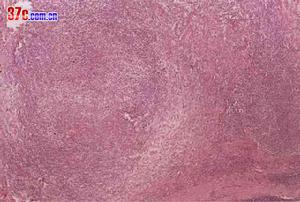

白血病慢性粒細胞白血病,簡稱慢粒,為慢性白血病中最常見一種類型。慢粒起病緩慢,早期多無明顯症狀,往往在體格檢查或其他疾病就診時偶然發現脾腫大或白細胞異常而獲得確診。在我國,慢性白血病中以慢粒最為常見,患者年齡在30-40歲者居多,20歲以下罕見。慢粒在臨床上可分為慢性期,加速期及急變期。病人出現急性白血病的臨床及血液等表現,稱之為慢粒急變。多數患者中數生存期為3-4年。慢粒發生急變後預後極差。

1.起病緩慢,部分病人早期可以沒有任何症狀。2.乏力:低熱、多汗或盜汗,體重減輕。3.最突出體徵為脾腫大,往往為巨脾,肝臟常有中度腫大,淺表淋巴結多不腫大。4.胸骨下部壓痛。5.急變期表現同急性白血病

白細胞1.慢性期:(1)臨床表現:無症狀或有低熱、乏力、多汗、體重減輕等症狀;(2)血象:白細胞計數增高,主要為中性中晚幼和桿狀粒細胞,原始細胞(Ⅰ型+Ⅱ型)≤5-10%,嗜酸粒細胞和嗜鹼粒細胞增多,可有少量有核紅細胞。(3)骨髓象:增生明顯至極度活躍,以粒系增生為主,中、晚幼粒和桿狀核粒細胞增多,原始細胞(Ⅰ型+Ⅱ型)≤10%。(4)染色體:有Ph染色體。(5)CFU-GM培養:集落或集簇較正常明顯增加。

2.加速期:具下列之二者,可考慮為本期。(1)不明原因的發熱、貧血、出血加重和或骨骼疼痛。(2)脾臟進行性腫大。(3)不是因藥物引起的血小板進行性降低或增高。(4)原始細胞(Ⅰ型+Ⅱ型)在血中及/或骨髓中>10%。(5)外周血嗜鹼粒細胞>20%。(6)骨髓中有顯著的膠原纖維增生。(7)出現Ph以外的其他染色體異常。(8)對傳統的抗慢粒藥物治療無效。(9)CFU-GM增殖和分化缺陷,集簇增多,集簇和集落的比值增高。

3.急變期:具下列之一者可診斷為本期。(1)原始細胞(Ⅰ型+Ⅱ型)或原淋+幼淋,或原單+幼單在外周血或骨髓中>=20%。(2)外周血中原始粒+早幼粒細胞>=30%。(3)骨髓中原始粒+早幼粒細胞>=50%。(4)有髓外原始細胞浸潤。(5)CFU-GM培養呈小簇生長或不生長。